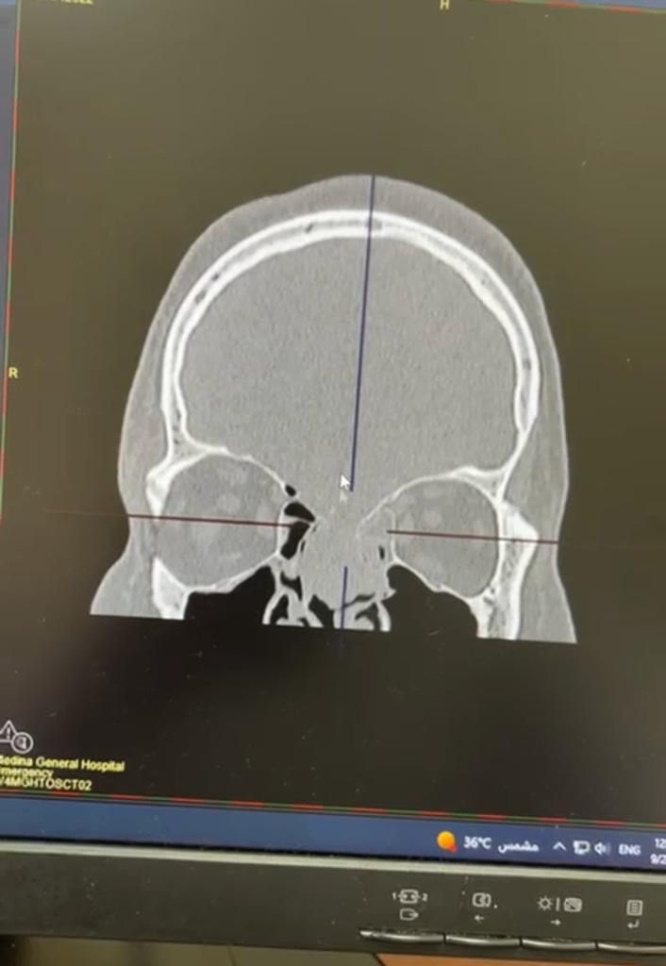

وأكد تجمع المدينة المنورة الصحي (غرب السعودية) أن المريض حضر لقسم الطوارئ في وضع صحي حرج وهو يعاني من سيلان السائل الدماغي من الأنف، حيث تم على الفور إجراء الفحوصات السريرية التي بينت وجود ثقب في قاع الجمجمة مع تورم داخل البطينيات الدماغية.

وعند استرجاع تاريخه الطبي تبين أن المريض عانى من توابع حادث مروري قديم أدى إلى انخساف في قاع الجمجمة، ثم تطورت الحالة بسبب وجود ورم في داخل البطينيات الدماغية، الأمر الذي أدى إلى انحباس في مجرى السائل الدماغي وارتفاع الضغط داخل الجمجمة.

الفريق الطبي المشترك في تخصص الأنف والأذن والحنجرة وجراحة المخ والأعصاب بمدينة الملك سلمان الطبية اتخذ قراراً بإجراء عملية لإزالة الورم وترقيع قاع الجمجمة من خلال تحديد موقع الثقب عن طريق جهاز الملاحة الدماغي في عملية تكللت بالنجاح. وأكد الفريق الطبي المعالج أن الحالة الصحية للمريض استقرت وأنه يواصل مرحلة النقاهة في المستشفى.